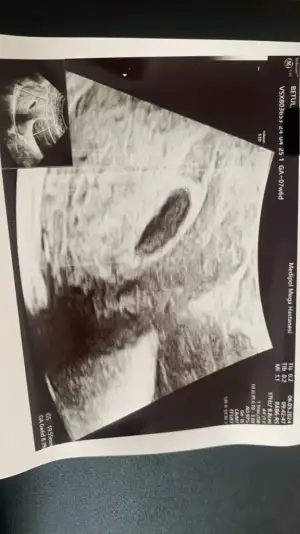

Nolur banada yardım edin . Ben bugün doktora gittim kese boyutu 18.42mm . Bebeği göremedi . Haftaya gel bebek yoksa kürtaj olucaksın dedi görseli ekliyorum. Başına gelen car mı??? 6+5 haftalık görünüyorKızlar selam yardımınıza ihtiyacım var.

Son adet tarihine göre kaç haftalıksiniz.Benim başıma geldi daha yeni düşük yaptımNolur banada yardım edin . Ben bugün doktora gittim kese boyutu 18.42mm . Bebeği göremedi . Haftaya gel bebek yoksa kürtaj olucaksın dedi görseli ekliyorum. Başına gelen car mı??? 6+5 haftalık görünüyor

Aynı şeyi kasım ayında yaşadım ne çektiğimi bir Allah bir ben bilirim ilk başta her iki günde bir beta verdim bana yükselmez dış gebelik dediler sonra yükseldi azar azar daha sonra kese oluşmaz dediler kese de oluştu ama kesenin içinde bebek oluşmadı uygulamaya göre 9+3 ama doktor keseye göre 6+2 dedi ve her iki günde bir ultrason yaptırdım iki farklı hastanede takip ettim ama en sonunda kürtaj dediler ilaç verip kürtaj yaptılarNolur banada yardım edin . Ben bugün doktora gittim kese boyutu 18.42mm . Bebeği göremedi . Haftaya gel bebek yoksa kürtaj olucaksın dedi görseli ekliyorum. Başına gelen car mı??? 6+5 haftalık görünüyor